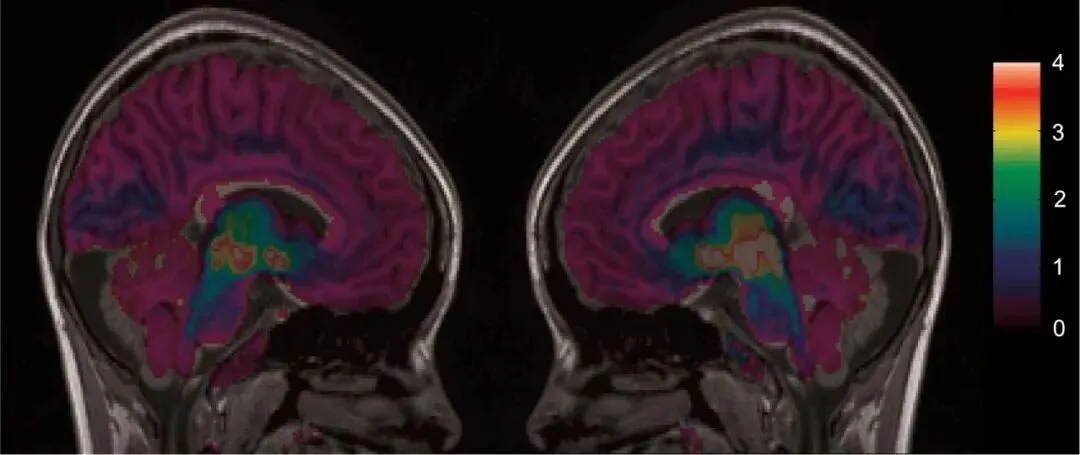

*一位 22 岁女性夏季无症状时(左图)和冬季出现严重抑郁症状(右图)的脑血清素转运蛋白结合情况

而脑血清素转运蛋白水平高→ 突触间隙活性血清素浓度严重且持续地下降